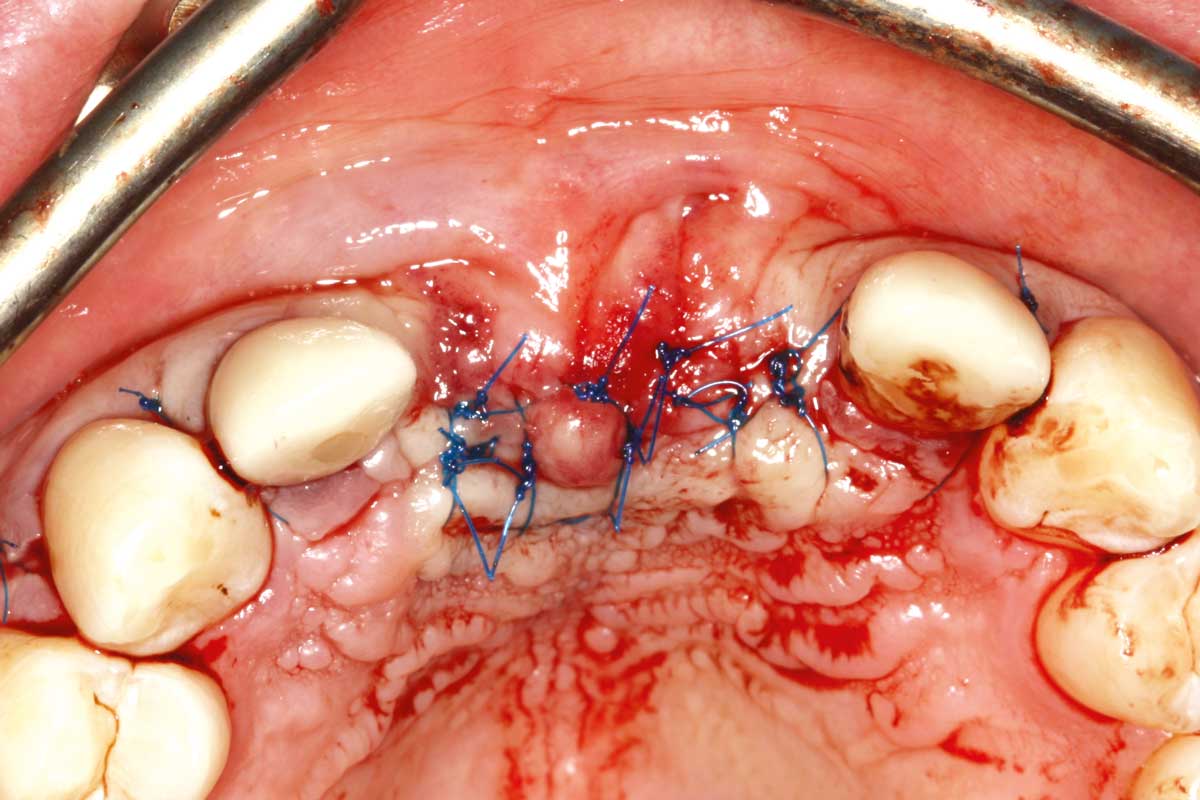

22/26 - Wound closure with 13 sutures

Ridge augmentation in the maxilla with maxgraft® bonebuilder in the aesthetic zone - Dr. M. Kristensen